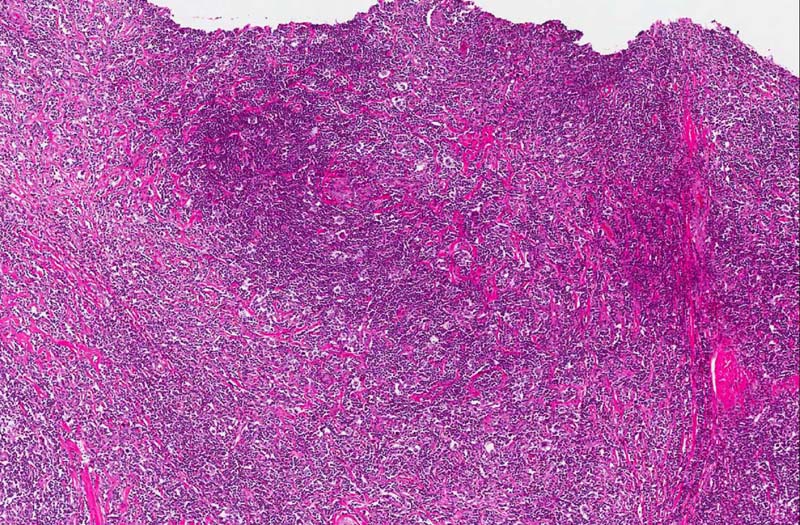

Diagnosis: Hodgkin lymphoma, nodular sclerosing type

Organ: Anterior mediastinum, thymus

• This tumor has several notable features. It is composed predominantly of small lymphocytes without any suggestion of lymphoma. Among these lymphocytes are scattered large, atypical cells with one or, less commonly, multiple nuclei (area 1). Many of the nuclei are lobulated and typically a prominent, eosinophilic nucleoli are present. The distribution of these cells are not homogeneous. They are hard to find in some areas. Also present in this backgound of lymphocytes are eosinophils (area 2). Again, their distribution is also non-homogeneous. The background of this tumor is very fibrotic and many nodules (arrow) surrounded by the fibrous tissue is present. These features are classic for nodular sclerosing type of Hodgkin lymphoma. The large atypical cells in fact are subclassified into the several categories as discussed below. Many of them can be found in this case.

• In order to make a diagnosis of the nodular sclerosing type, there must be collagen bands that surround at least one nodules and lacunar type Reed-Sternberg cells.